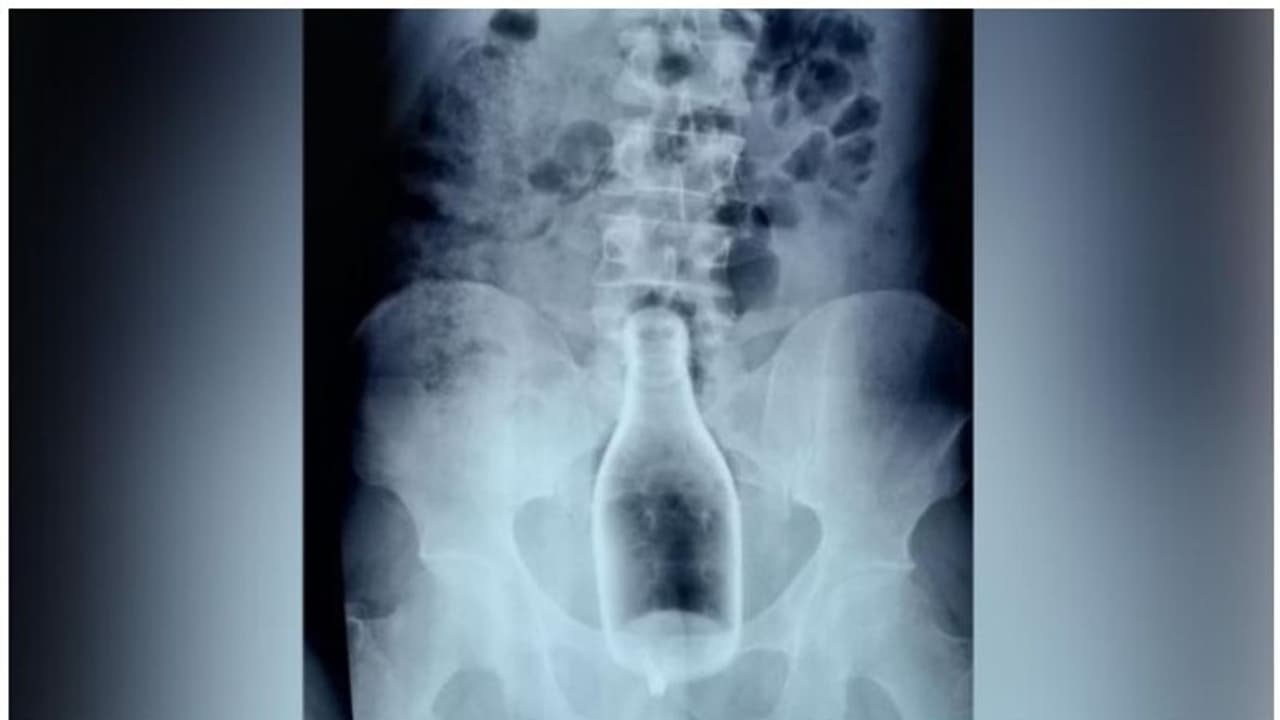

നാഗപട്ടണം: മലദ്വാരത്തിലും വയറിലും അതികഠിനമായ വേദനയുമായി എത്തിയ ഇരുപത്തൊമ്പതുകാരന്റെ വയറിനുള്ളില് നിന്ന് നീക്കിയത് മദ്യക്കുപ്പി. മെയ് 27നാണ് നഗരൂര് സ്വദേശിയായ യുവാവ് ആശുപത്രിയിലെത്തിയത്. എക്സ്റേയിലാണ് 250 മില്ലിയുടെ ഗ്ലാസ് കുപ്പി കണ്ടെത്തിയത്. എക്സ് റേ കണ്ട് ഞെട്ടിയെന്ന് നാഗപട്ടണം സര്ക്കാര് ആശുപത്രിയിലെ ജനറല് സര്ജനായ ഡോ എസ് പാണ്ഡ്യരാജ് ദി ന്യൂസ് മിനിറ്റിനോട് പ്രതികരിച്ചു. ആശുപത്രി ജീവിതത്തിനിടെ ഇത്തരമൊരു സംഭവം ആദ്യമാണെന്ന് ഡോക്ടര് പറയുന്നു.

ആരോഗ്യ പ്രവര്ത്തകരുടെ വിശദമായ ചോദ്യം ചെയ്യലിലാണ് സംഭവത്തെക്കുറിച്ച് കൂടുതല് വിശദമാകുന്നത്. യുവാവ് സ്വയമാണ് മദ്യക്കുപ്പി മലദ്വാരത്തില് കുത്തിക്കയറ്റിയത്. മദ്യലഹരിയിലായിരുന്നു കുപ്പി മലദ്വാരത്തില് കയറ്റിയത്. എന്നാല് പിന്നീട് കുപ്പി പുറത്തെടുക്കാനുള്ള ശ്രമങ്ങള് പരാജയപ്പെടുകയായിരുന്നു. പുറത്തെടുക്കാന് സാധിച്ചില്ലെന്ന് മാത്രമല്ല കുപ്പി കൂടുതല് ഉള്ളിലേക്ക് കയറുകയും ചെയ്തു. വീട്ടുകാരോട് വയറുവേദനയുടെ കാരണം ഇതാണെന്ന് ഇയാള് വ്യക്തമാക്കിയിരുന്നില്ല. രണ്ട് ദിവസം കുപ്പി വയറില് കുടുങ്ങിയതോടെ വേദന അസഹ്യമായി. ഇതിനേത്തുടര്ന്നാണ് വീട്ടുകാര് ഇയാളെ ആശുപത്രിയിലെത്തിച്ചത്.

കൊറോണ വൈറസ് പരിശോധന പൂര്ത്തിയാകാതെ സര്ജറി ചെയ്യേണ്ടെന്നായിരുന്നു ആദ്യ തീരുമാനമെങ്കിലും കുപ്പി ചില്ലുകൊണ്ടുള്ളതിനാലും കൂടുതല് ആന്തരിക മുറിവുകള് അവഗണിക്കാനുമായി ഇയാളെ ശസ്ത്രക്രിയയ്ക്ക് വിധേയനാക്കുകയായിരുന്നു. രണ്ട് മണിക്കൂര് നീണ്ട ശസ്ത്രക്രിയയിലൂടെയാണ് കുപ്പി പുറത്തെടുത്തത്.